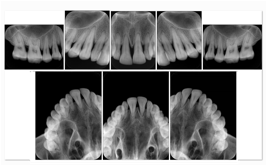

1. A patient in rural Canada visits a general ophthalmologist and is found to have diabetic macular edema. The general ophthalmologist would like to discuss the case with a retina specialist before performing laser surgery. A fluorescein angiogram is done with multiple retinal images taken in a timed series after an intravenous injection. The images along with a Structured Display are shared via a Health Information Exchange with a retina specialist in Calgary, who opens them using his Ophthalmology EMR software and consults via phone with the general ophthalmologist. Both physicians view the images in the same layout so the retina specialist can provide accurate guidance for treating the patient.

2. A patient in rural Iowa visits his primary care physician for management of diabetes. Three non-mydriatic (patient's eyes are not dilated) photographs are taken of the back of each eye, and forwarded electronically along with a Structured Display to an ophthalmologist in Iowa City. The ophthalmologist reads the photos in an agreed upon layout so there is no mistake about what portion of which eye is being viewed. The ophthalmologist is able to tell the primary care physician that his patient does not need to come to Iowa City for face to face ophthalmologic care, but that there is a particular view of the left eye that should be photographed again in 6 months.

Ophthalmic Retinal Study Structured Display

Figure OO-3. Ophthalmic Retinal Study Structured Display